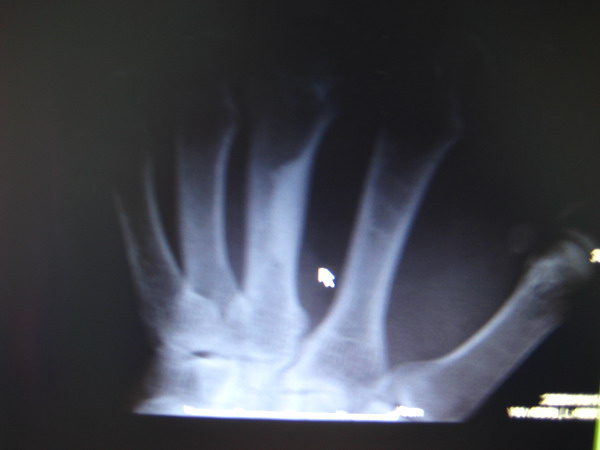

男 53 左手掌指关节肿胀 疼痛

片子太黑,关节看不清。箭头所指为局限性皮质增厚,无意义,多为良性皮质缺损愈后改变。鉴别:蜡泪样骨病、内生骨瘤。

看到了一个局限性的致密影,但是意义不大

支持考虑局限性皮质增厚。

局限性皮质增厚

局限性皮质增厚。

局限性皮质增厚??---请结合临床!!

局限性皮质增厚。鉴别内生软骨瘤

指跖骨的局限性皮质增厚,多考虑为正常变异。